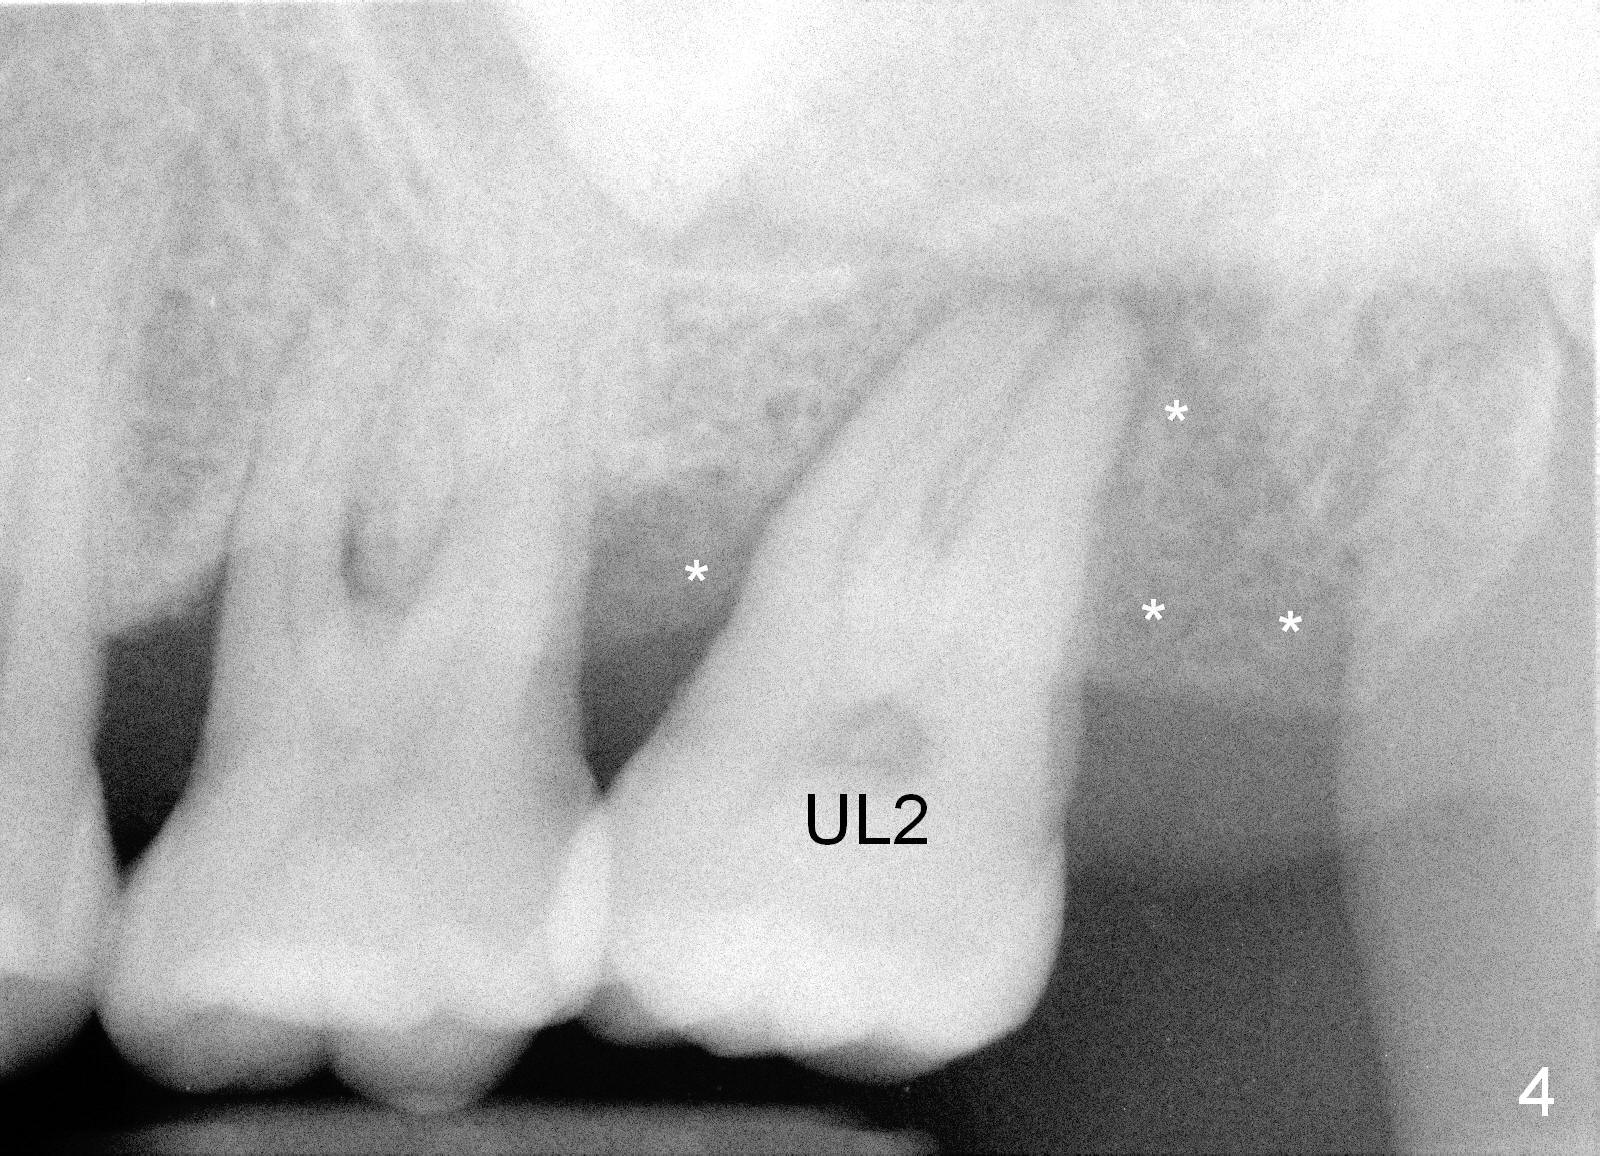

A 49-year-old lady is scared of dentistry. She presented with chronic periodontitis 7 years ago. The lower right 2nd molar had been missing (Fig.1 LR2), while the upper right 2nd molar shifted distally (arrow). Her chief complaint was mobility of #15 (Fig.2,4 UL2 with severe bone loss (*)). The tooth was extracted with expectation of return for implant placement in 6-8 weeks.

When she returns 7 years later, the tooth #2 has perio abscess with severe bone loss (Fig.3). She refuses to take antibiotic for infection control, but agrees to have immediate implant for #2 because of 1-staged surgery (Fig.5 I: 8x17 mm; A: abutment; P: bone powder (graft)). She is aware of delayed implants at the sites of #15 and 31 later. The bone height at the site of #15 reduces from 12 mm (Fig.4) to 7 mm (Fig.6) in 7 years.